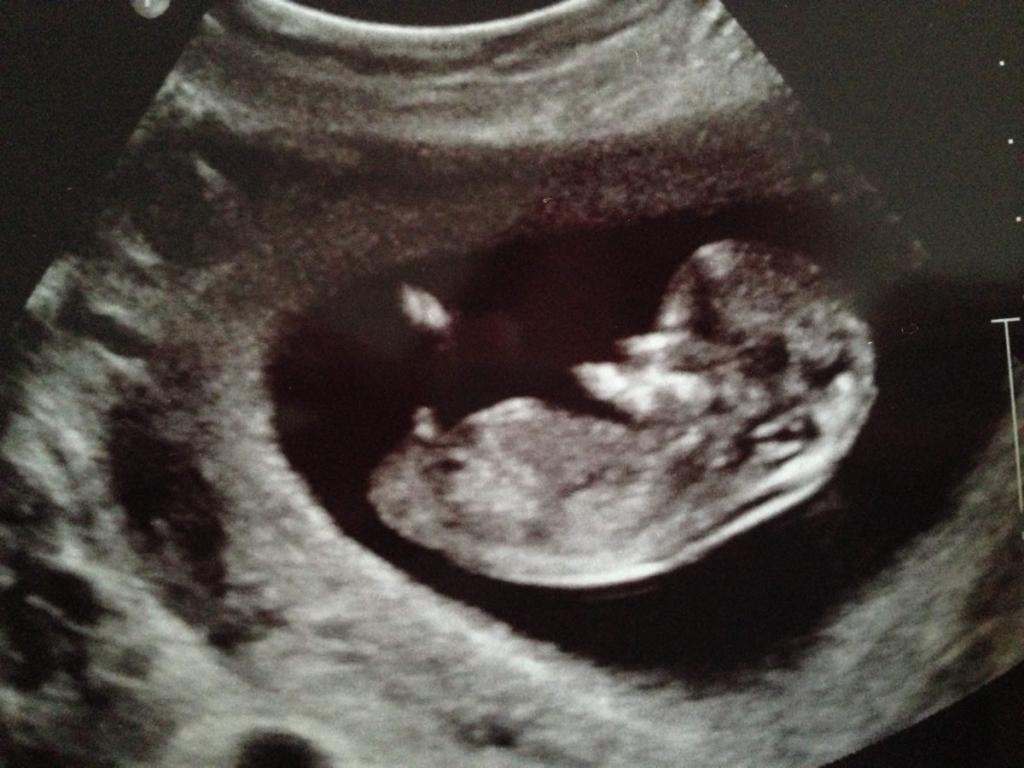

Thanks a lot for taking a look for me. Here is another one taken at the same time, however I think the baby is turned a little bit so it's not quite flat on his/her back.

Attachment 7237

The last one looks all boy.

Forks can be seen on both boy and girl nubs. It doesn't look tricky to me as it is clearly angled up. 2nd pic has a textbook boy nub. Congrats!